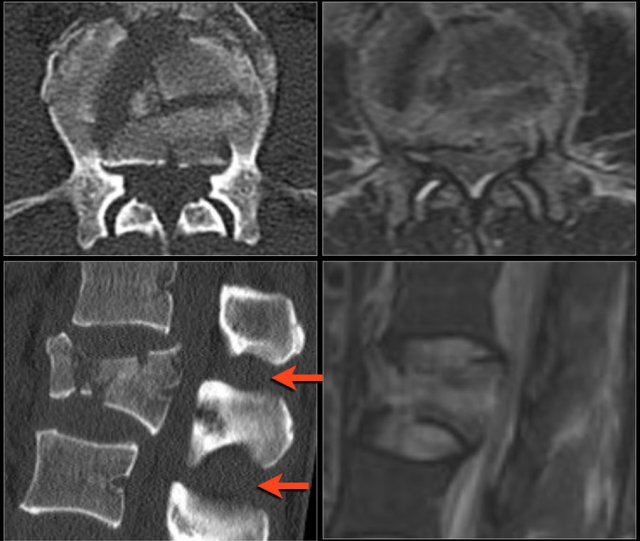

Widening of the interpedicular distance

Widening of the interpedicular distance, often a result of the sagittal fracture, is seen in 80% of burst fractures.

The lateral view shows the typical features of a burst fracture.

On the AP-view notice the subtle widening of the interpedicular distance compared to the levels above and below.

The axial CT and MRI in the same patient show the displaced fragment pressing on the thecal sac.

On the sagittal CT and MRI there are no signs of posterior ligamentous injury.

The anterior longitudinal ligament is disrupted.

The right facet joint looks a bit widened on the CT and there is some fluid in the joint on the MRI.

If there was a lot of fluid in the joint, we should call this indeterminate.

In this case we are not sure.